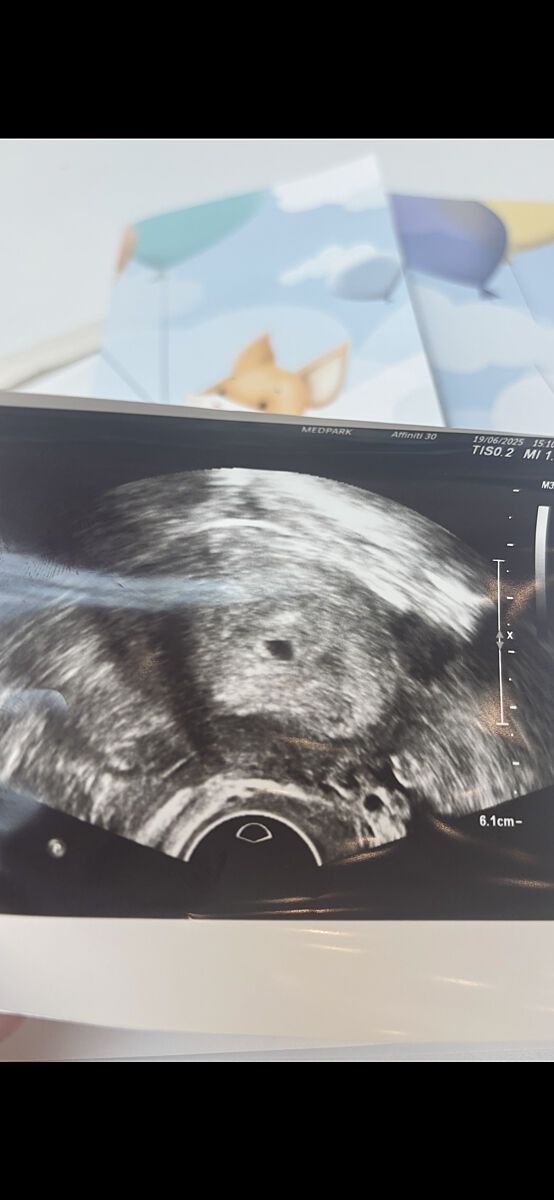

Може бути завмерла вагітність?

Після ЭКО 2 червня була підасдка 5-денного ембріона. 19 була на узі і побачили крапочку, але в середині порожньо(( я начиталась, що можлива завмерла вагітність(( у мене немає токсикозу, взагалі відчуваю себе нормально. Чомусь почала переживати((

Ну на вашому терміні тільки крапочку там і могли побачити на УЗД.

Якщо прям дуже тривожитесь, то сходіть на УЗД.